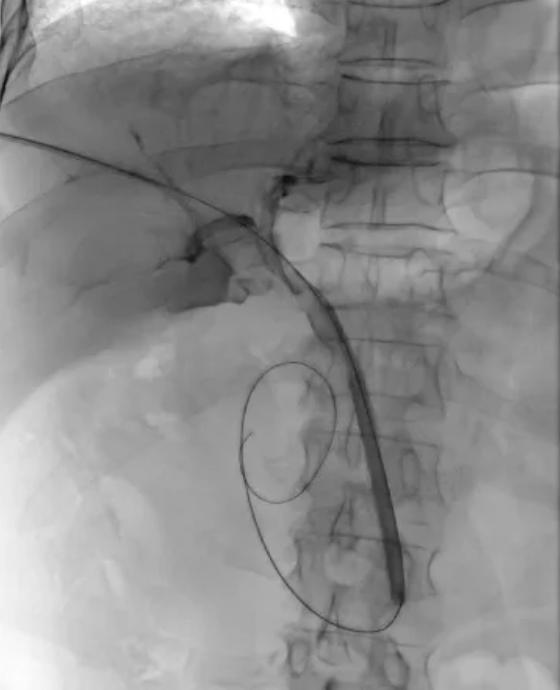

术中造影:6F球囊推石。

手术在局部麻醉下进行。在超声和X线透视的精准引导下,任虎虎副主任医师团队通过一个仅几毫米的穿刺点,成功建立了经皮经肝至胆总管的微细通道。

核心步骤随之展开:一根在介入手术中极为常见的6F普通血管成形球囊,沿着通道被送至结石下方。连接压力泵,球囊缓缓张开,形成一个柔和的“推力面”。在透视屏幕的监视下,医生如同一位沉稳的“推手”,运用巧劲,稳健地将这颗困扰多日的结石,轻轻地“推”过了Oddi括约肌,进入了宽阔的十二指肠。